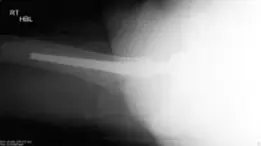

صورة توضيحية لـ مفصل الورك الصناعي الهجين: حل شامل ومتقدم لآلام المفاصل المعقدة

صورة طبية: مفصل الورك الصناعي الهجين: حل شامل ومتقدم لآلام المفاصل المعقدة